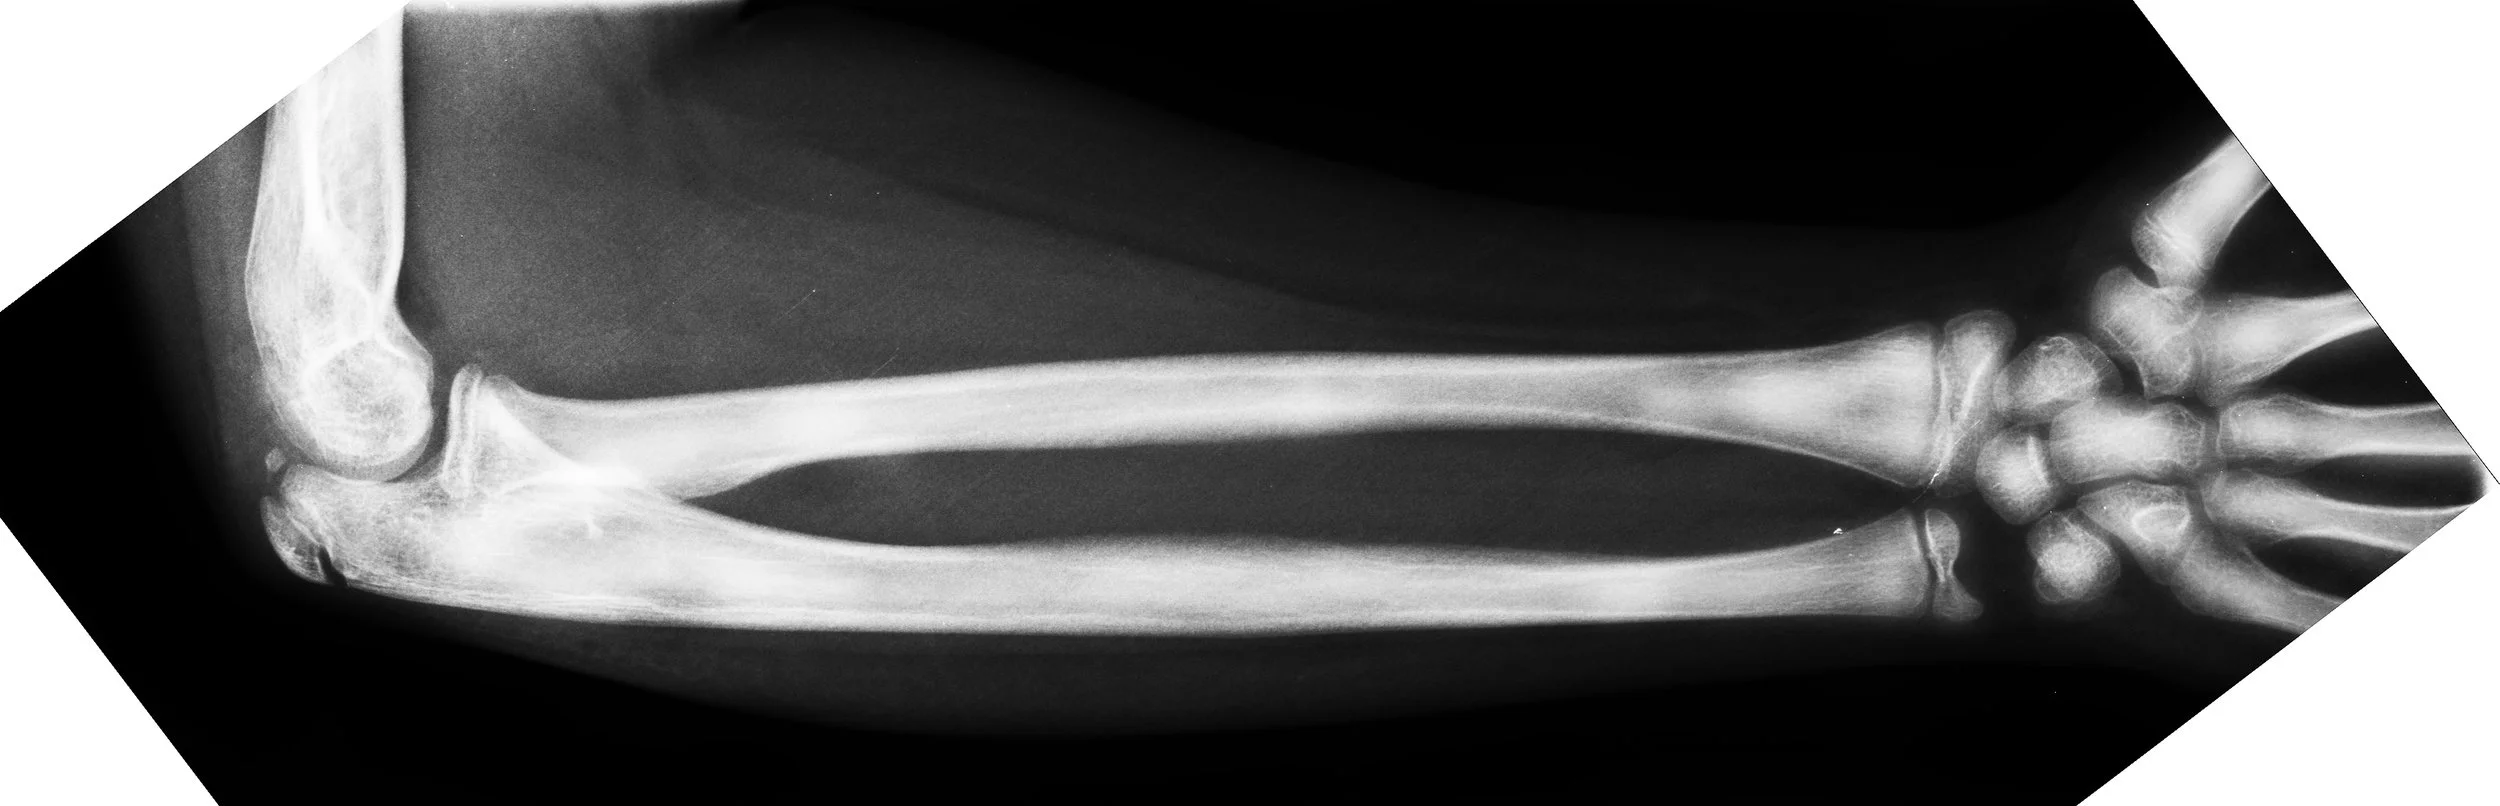

Defining Practice - 3D Scoliosis Spine